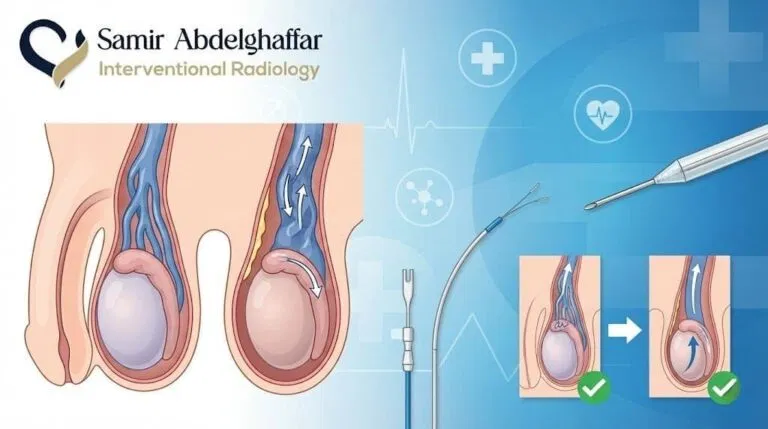

كيف يتم إجراء عملية الأشعة التدخلية لعلاج دوالي الخصية؟

العملية تبدأ بتخدير المنطقة المحددة موضعيًا. بعد ذلك، يقوم الطبيب بإدخال قسطرة عبر فتحة صغيرة في الجلد، ويتم توجيهها إلى الأوردة المصابة داخل الصفن باستخدام الأشعة. يتم حقن صبغة طبية لتحديد موقع الأوردة بدقة. ومن ثم، يقوم الطبيب بسد الوريد المصاب باستخدام لولب، لفافات معدنية، أو مواد حقن طبية لمنع ارتجاع الدم. بعد الانتهاء، يتم سحب القسطرة وضغط مكان الدخول لبضع دقائق لمنع النزيف.

يمكن علاج دوالي الخصيتين بالقسطرة على الناحية اليسرى واليمنى من فتحة واحدة، وفي أغلب الحالات تحتاج الخصية اليسرى للعلاج، ولكن يمكن علاج الناحيتين إذا كانت الدوالي موجودة أيضًا في الخصية اليمنى. يتم علاج الناحيتين من فتحة واحدة قد تكون في أعلى الفخذ الأيمن، أو الأيسر، أو من خلال اوردة الذراع، أو الرقبة، كما يمكن علاج دوالي الخصية بالقسطرة و بدون تدخل جراحي وبنسب نجاح عالية ، بغض النظر عن درجة الدوالي سواء الدرجة الأولى أو الثانية أو الثالثة.

ما هي الاشعة التداخلية المستخدمة في علاج دوالي الخصية؟